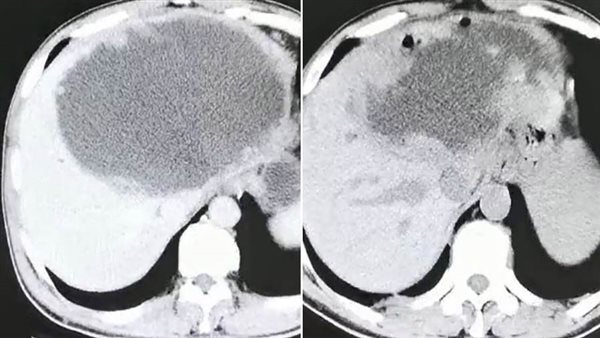

وذهب "شاي" إلى المستشفى بعد أربعة أشهر، عقب معاناته من قشعريرة وحمى شديدة لمدة ثلاثة أيام. وذهل الأطباء عندما اكتشفوا أن كبد المريض يحتوي على كتلة ضخمة مليئة بالصديد يبلغ طولها 19 سم وعرضها 18 سم، وفقا للتقرير. وحاول الجراحون في البداية تقليل النتوء الاجتياحي مثل الكيس، عن طريق تجفيف الكتلة من السوائل، ولكنهم أدركوا بسرعة أن العدوى شديدة جدا، وقرروا قطع نصف الكبد. وكشف فحص لاحق أن الكتلة كانت تحتوي على عدد لا يحصى من البيض الذي وضعه متفرع الخصية الصيني أو وشيعة الكبد الصينية، وهو طفيل موجود في المأكولات البحرية النيئة. واستنتج الأطباء أن "شاي" أصيب بالطفيلي بعد تناول الأسماك غير المطبوخة جيدا أثناء رحلته إلى سيتشوان.